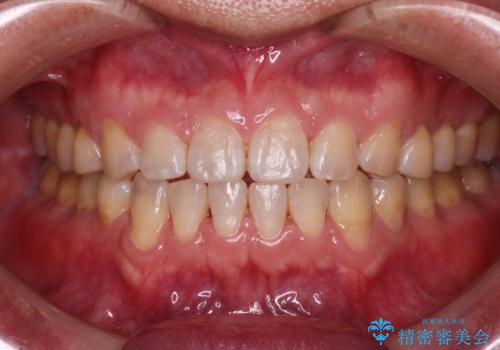

[マウスピース矯正] がたがたの歯並びをきれいにしたい

![[マウスピース矯正] がたがたの歯並びをきれいにしたいの症例 治療後](https://seimitsushinbi.jp/wp/wp-content/uploads/2025/06/IMG_0002-2-500x350.jpg?v=1750323305)